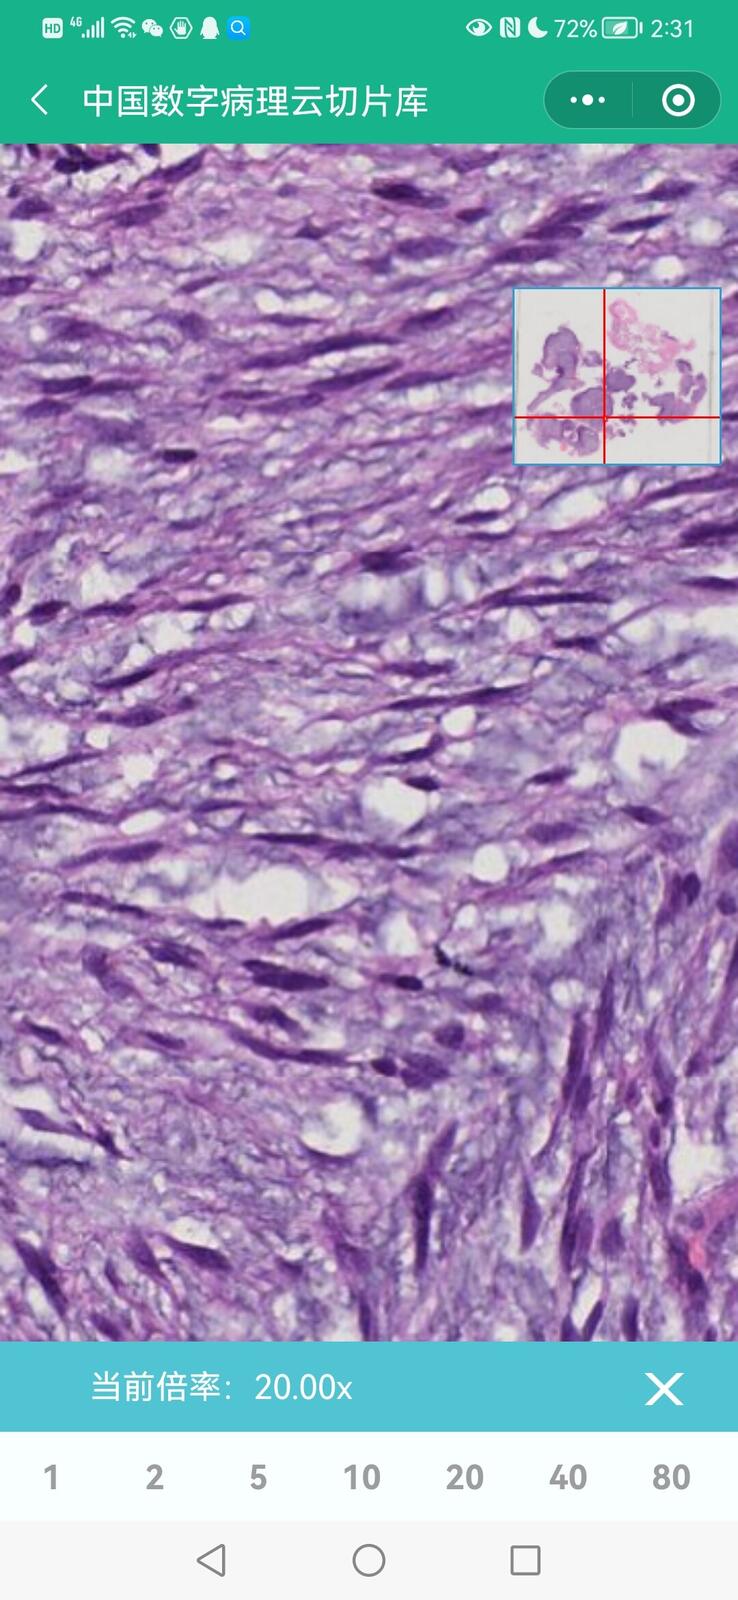

乳腺多形性脂肪肉瘤

乳腺叶状囊肉瘤